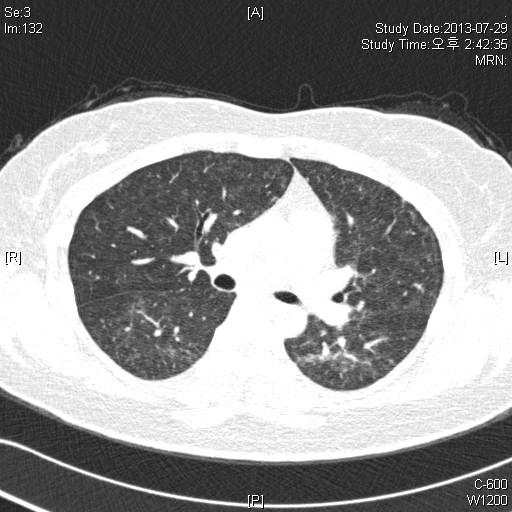

39¿©ÀÚ È¯ÀÚ·Î, Rt breast cancer Áø´ÜÇÏ¿¡ 2013³â 3¿ùºÎÅÍ Ç×¾Ï Ä¡·á ¹ÞÀº ȯÀÚ·Î,

dyspnea on exertion ¾ÇÈ­µÇ¾î È£Èí±â³»°ú ¹æ¹®ÇÔ.

CRP 0.68 mg/l, Procalcitonin<0.05 mg/dl

CBC: 6000-12.1-246k(neutrophil:71.8%, eosinophil 1.0%)

PFT: FVC/FEV1/Ratio: 2140(56%)/ 1810(60%)/ 84% (3ÃÊ ÀÌ»ó ºÒÁö ¸øÇÔ)

Bronchodialtor response (-)